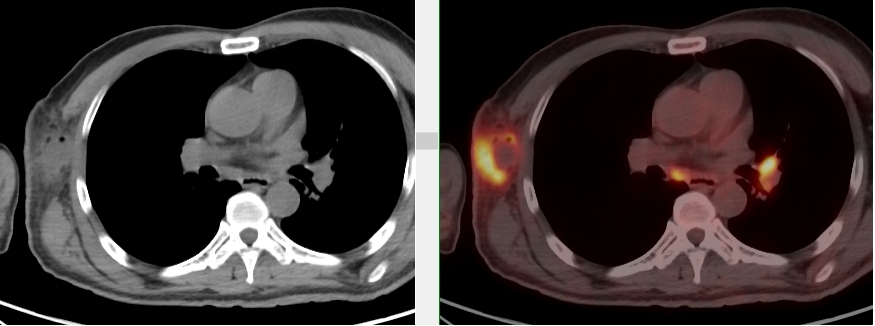

完善PET/CT檢查示:右側腋窩、雙側中下頸部、縱隔、雙側肺門多發MT,建議淋巴結活檢。后患者行右腋窩淋巴結切除活檢術,經北京大學第三醫院病理科會診示:右腋窩淋巴結惡性腫瘤,呈淋巴竇內生長模式,瘤細胞呈上皮樣,異型性明顯,伴中性粒細胞浸潤。結合病史及免疫組化,考慮為SMARCA4(BRG1)缺失的胸部腫瘤,伴神經內分泌標記表達。

本例為罕見病理類型的腫瘤,影像學表現無明顯特異性,診斷困難。強化CT和穿刺病理已基本明確為惡性腫瘤,行PET/CT檢查一是為了全身檢查,完善分期,二是根據PET代謝情況指導進行生物靶區活檢,進一步明確病理診斷。最終,PET/CT除縱隔病變外發現更多頸胸部淋巴結代謝異常,綜合考慮后對腋窩淋巴結進行切除活檢,最終得到病理證實。